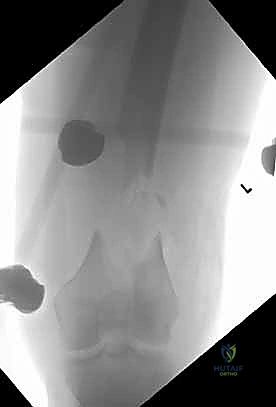

- الأشعة السينية (X-Rays): أخذ صور من زوايا متعددة (أمامي خلفي، وجانبي) لتحديد موقع الكسر ونوعه.

- الأشعة المقطعية (CT Scan): وهي ضرورية جداً في كسور عظم الفخذ البعيدة، خاصة إذا كان الكسر يمتد إلى داخل مفصل الركبة (Intra-articular fractures). تساعد الأشعة المقطعية الدكتور هطيف على بناء نموذج ثلاثي الأبعاد للكسر، مما يسهل التخطيط الجراحي وتحديد أماكن وضع المسامير بدقة.